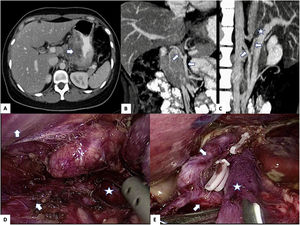

A 31-year-old woman presented with a 7-cm lesion in the lesser curvature of the stomach with possible invasion of the pancreas and retroportal right hepatic artery of the superior mesenteric artery. After neoadjuvant treatment, total gastrectomy with laparoscopic distal splenopancreatectomy (histology: signet ring cell adenocarcinoma, T4N3M0) was performed using a primary approach of the gastroduodenal artery for lymphadenectomy (groups 8 and 9). The postoperative evolution was favorable, and the patient continued to be disease-free 6 months later (Fig. 1).

The primary approach of the gastroduodenal artery in lymphadenectomy for gastric cancer guarantees optimal visualization of the structures and possible vascular anomalies, thereby avoiding injuries and ensuring oncological results.